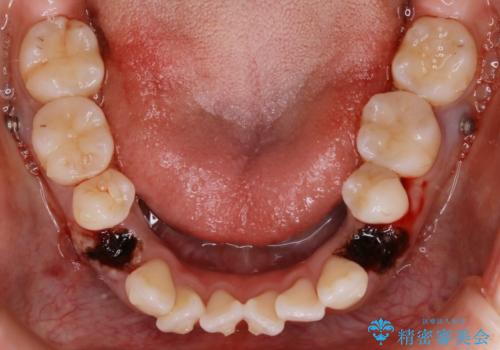

- 前歯のガタつき・噛み合わせの不調を主訴にご来院されました。

患者様のお仕事柄、目立たない装置で矯正したいとのご要望があり、今回はインビザラインを用いて抜歯矯正を行うこととなりました。

本来、抜歯によって得られる大きなスペースのコントロールはワイヤー装置の方が得意とされていますが、こちらの患者様のように犬歯が大きく手前に傾斜していて奥歯の噛み合わせにそれほど問題がないケースではマウスピース装置でも十分にコントロールできることが予測されます。